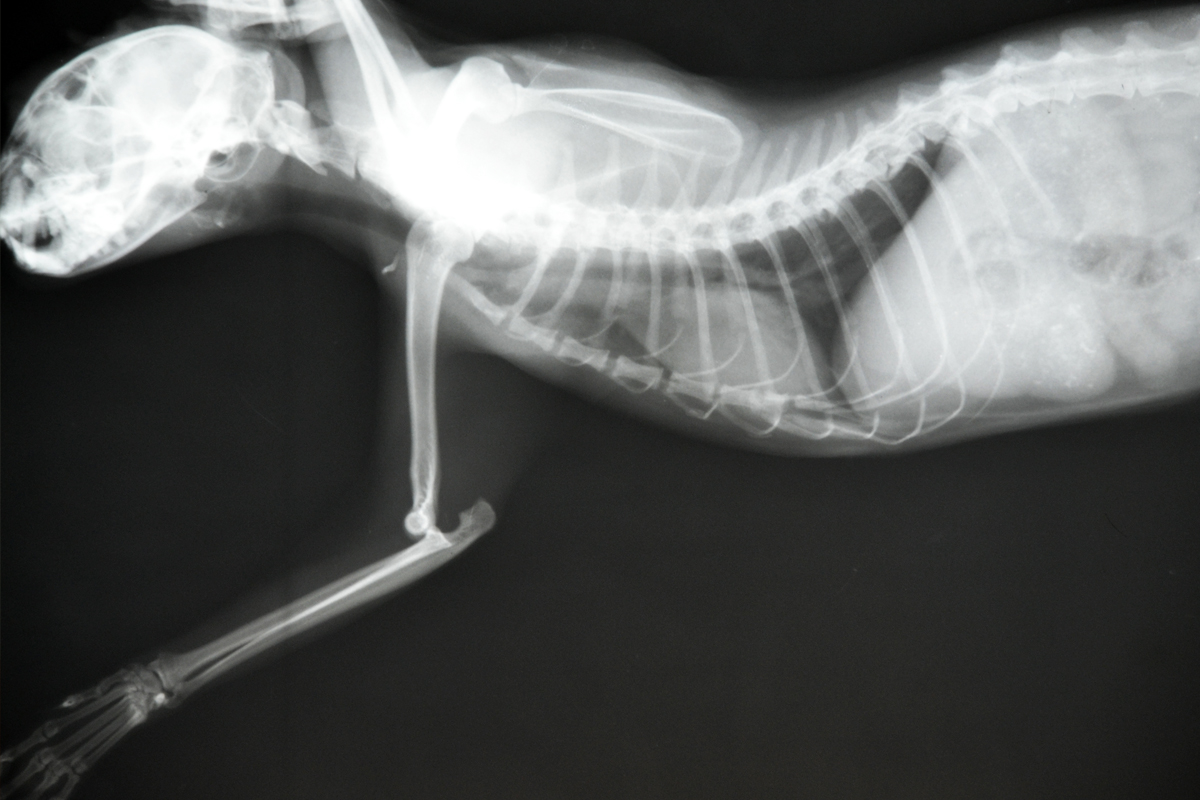

Рентгеновские снимки анатомии собак: строение и здоровье